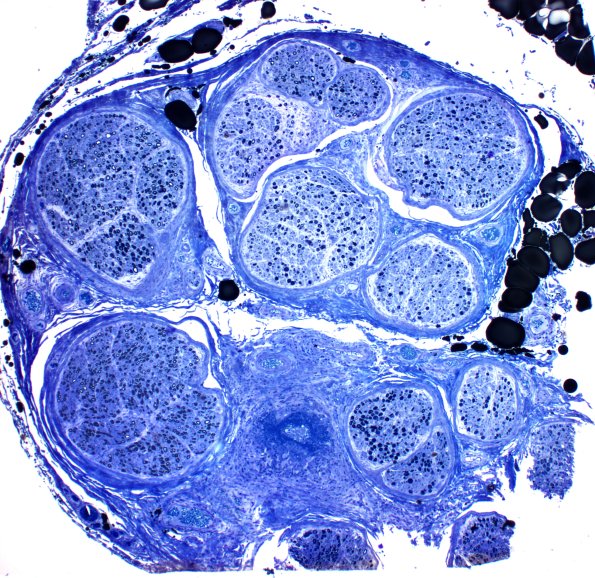

Washington University Experience | PERIPHERAL NEUROPATHY | 11 VASCULITIS - VASCULOPATHY | 4 Polyarteritis nodosa | 1C4 PAN (Case 1) Plastic 4X a

1C4,5 At another level the vessel shows destruction and dark blue fibrin deposition. (Plastic section)